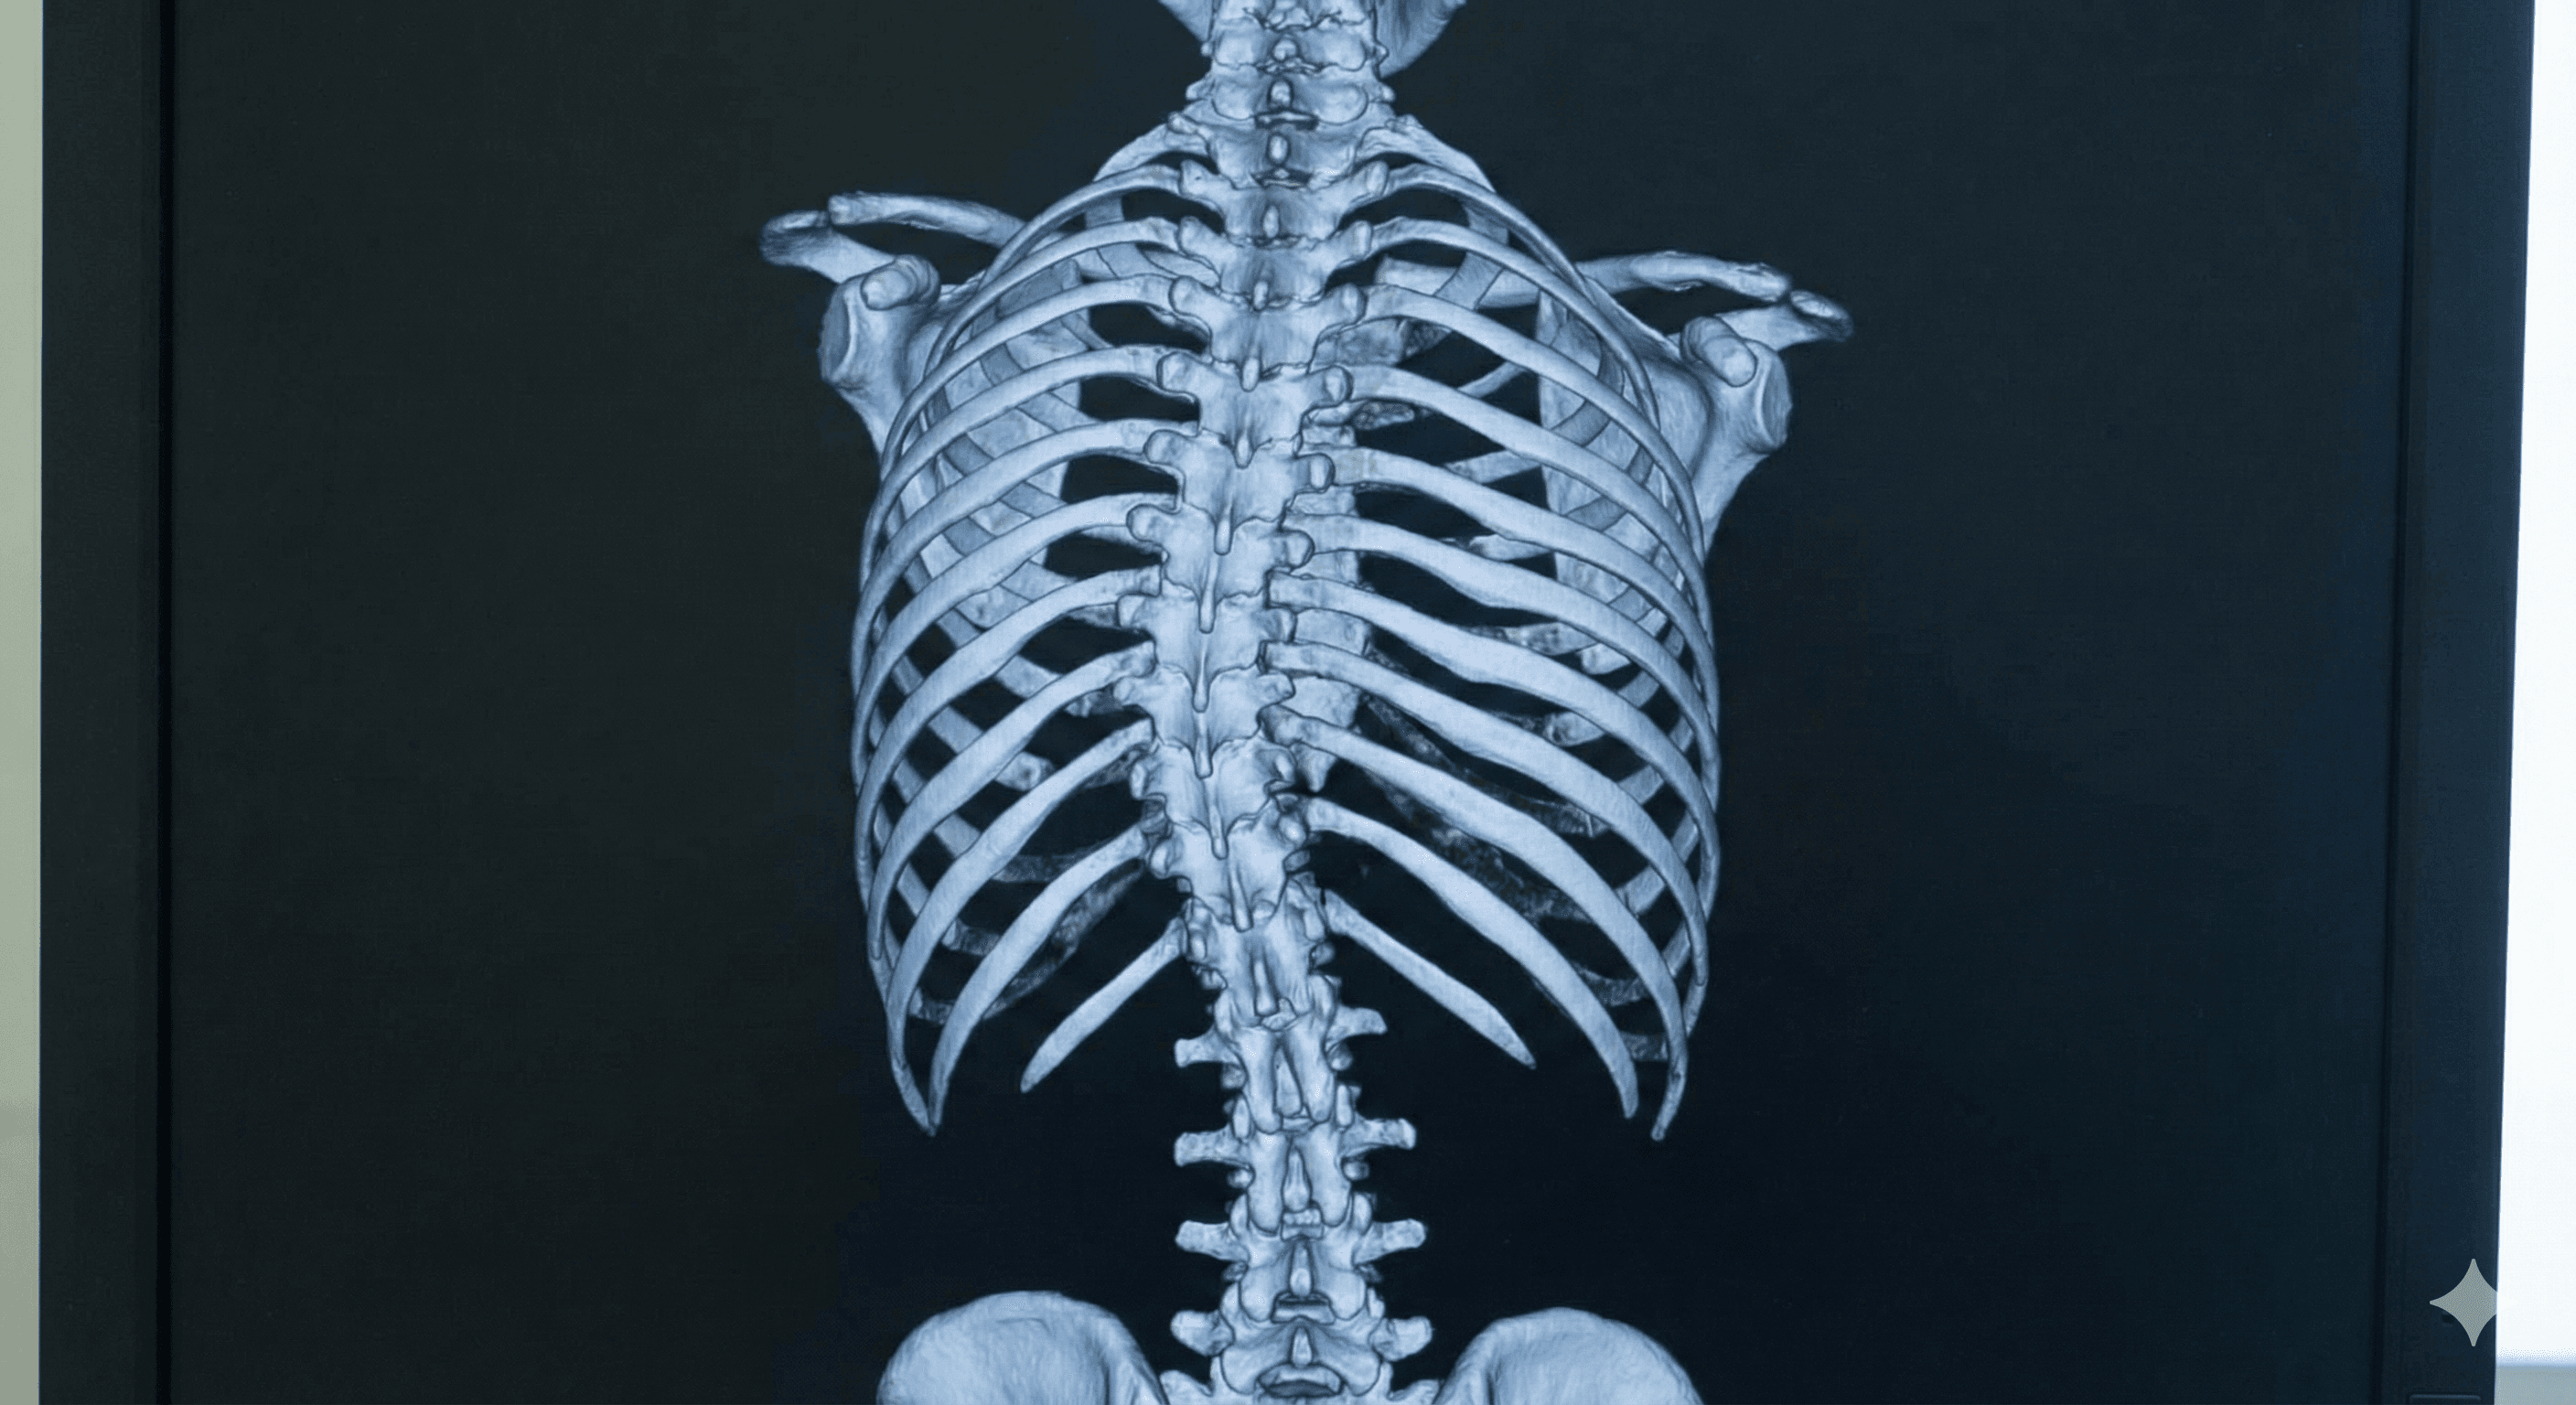

Curvatura anormal de la columna vertebral en forma de 'S' o 'C', que puede causar dolor y problemas posturales.

Leer más